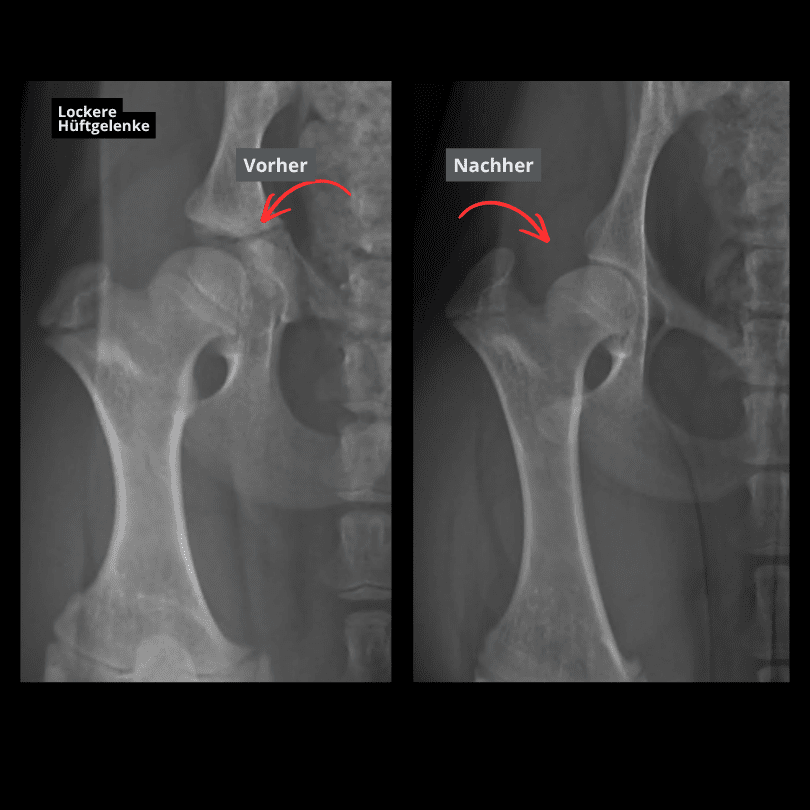

Hip dysplasia (HD) is one of the most common orthopaedic conditions in dogs. It involves abnormal development of the hip joint with insufficient coverage of the femoral head.

Special examination techniques are used in early diagnostics, e.g.:

- clinical stability tests (Ortolani test)

- growth and development assessment

- distraction view

- hip arthroscopy

The earlier laxity is detected, the better the treatment options—especially during growth.

- A prerequisite is early diagnosis of hip joint laxity, e.g. by X-ray and determining the distraction index (PennHIP method)